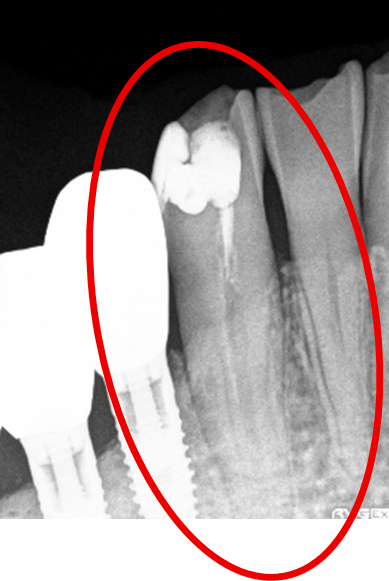

女性 Sさん 50代 (オールセラミック冠)

主訴

左上の差し歯がとれたままになっている。

治療内容

レントゲンを撮り詳しく診てみると、歯根が破折して保存することができず、抜歯する必要があることがわかりました。抜歯後、オールセラミックブリッジで補綴(欠損した部分を人工物で補う)しました。ブリッジの支台になっている後方の歯は、根尖性歯周炎(根の先端で問題を起こしている)でしたので、根管治療をしています。

所感

抜歯後、欠損部分を補う方法には、1本だけの部分入れ歯、ブリッジ、インプラントの3つの方法があります。この患者さんは、ブリッジを選択されました。メタルフリーの治療を希望されましたので、土台をファイバーコアにし、オールセラミックのブリッジをかぶせました。患者さんは、お口の中の金属を徐々に減らしていきたいということです。体全体の健康のことを考えると正しいことです。

オールセラミック冠(失活歯)1本:¥104,500(税込)

オールセラミック冠(生活歯)1本:¥93,500(税込)

ポンティック1本:¥93,500(税込)

合計:¥291,500(税込)